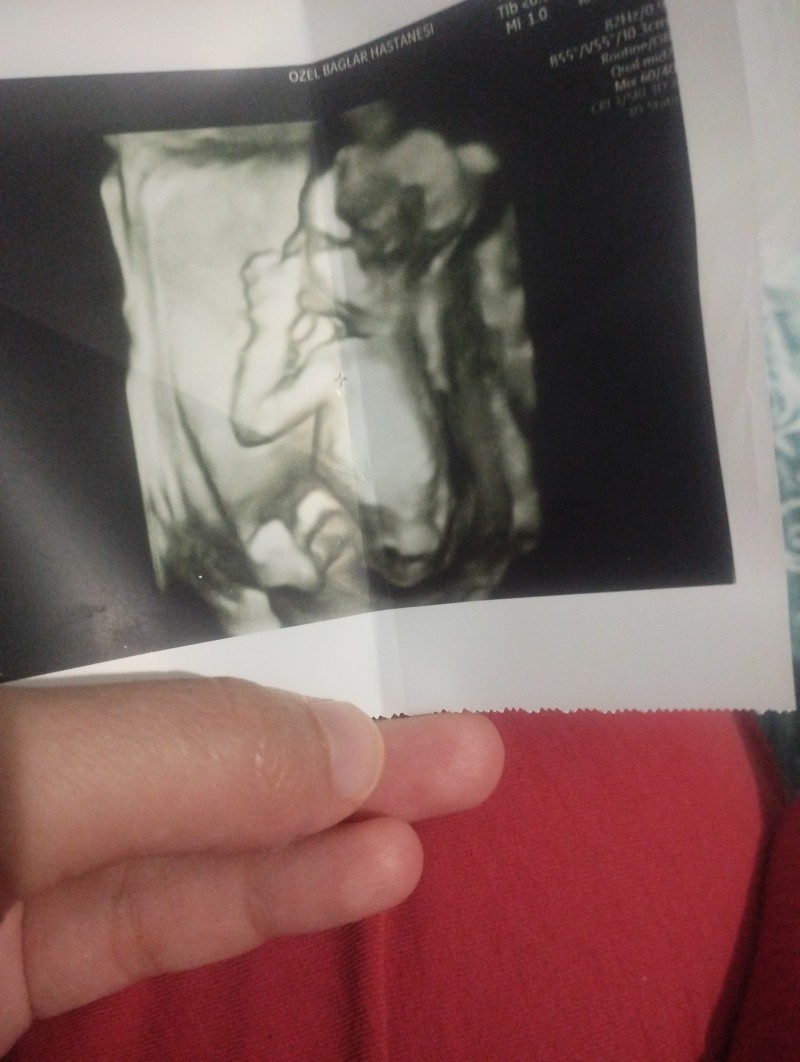

cinsiyet tahmini yapabilir misiniz

Popişini dönmüş ama erkek sanki. Bayağı büyük duruyor doktorun demesi lazim çoktan

Erkek hatlarına benziyor valla